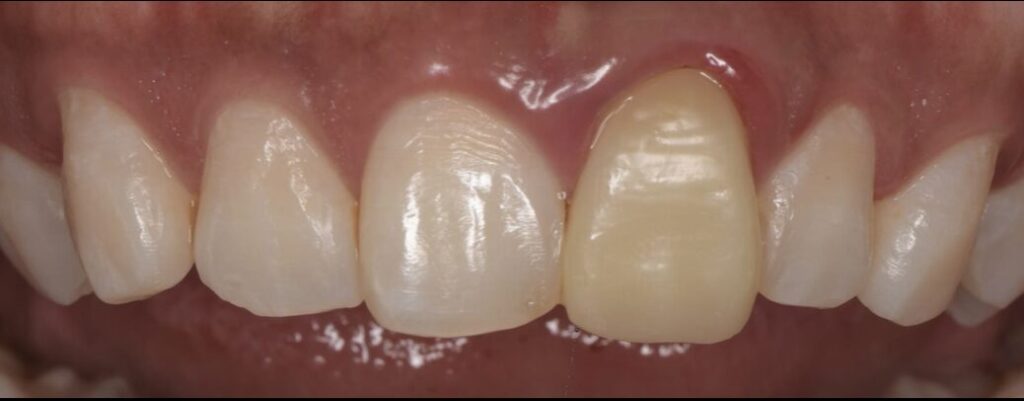

Before

初診時の口腔内写真とデンタルX線写真